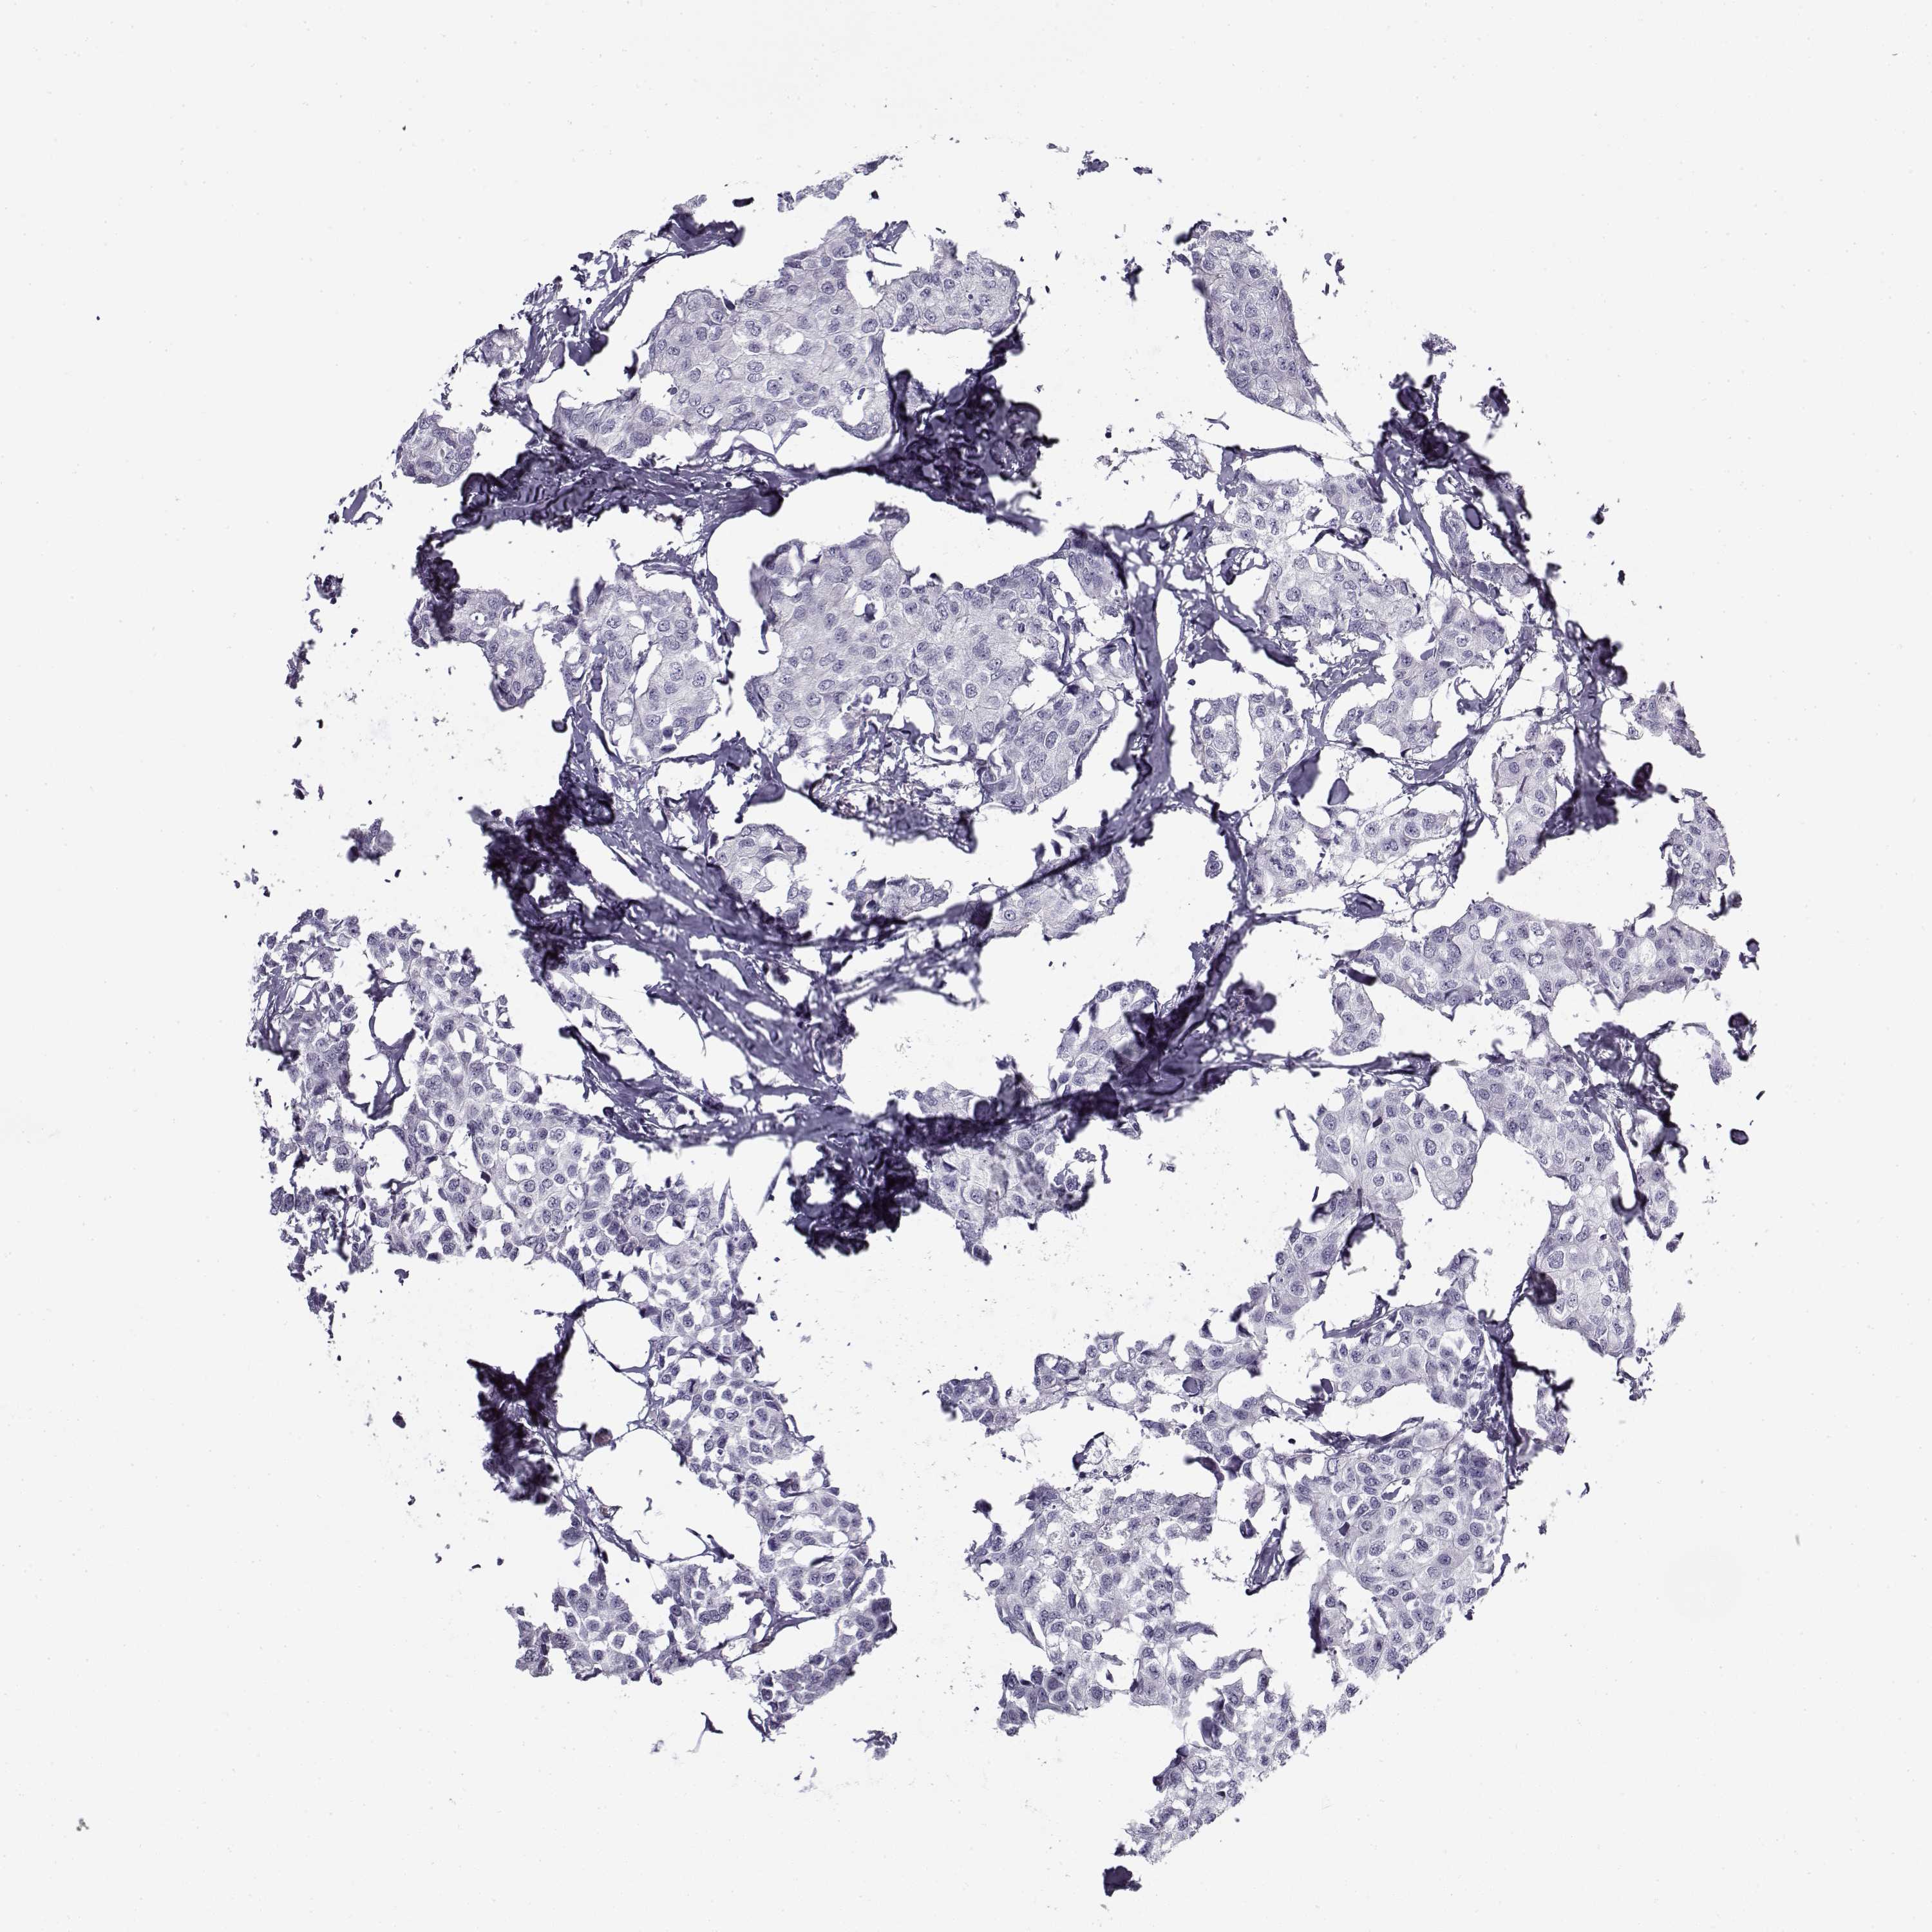

BRCA TCGA BRCA VALIDATION PROTEIN EXPRESSION

Breast cancer

Human cancer